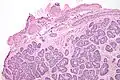

Micrograph of a Sertoli cell nodule. H&E stain. -

Micrograph of a Sertoli cell nodule. H&E stain.

Sertoli cell nodules are unencapsulated nodules that consist of:[2][3][4]

- cells arranged in well-formed tubules (that vaguely resemble immature Sertoli cells), with

- bland hyperchromatic oval/round nuclei that are stratified, and

- may contain eosinophilic (hyaline) blob in lumen (centre).